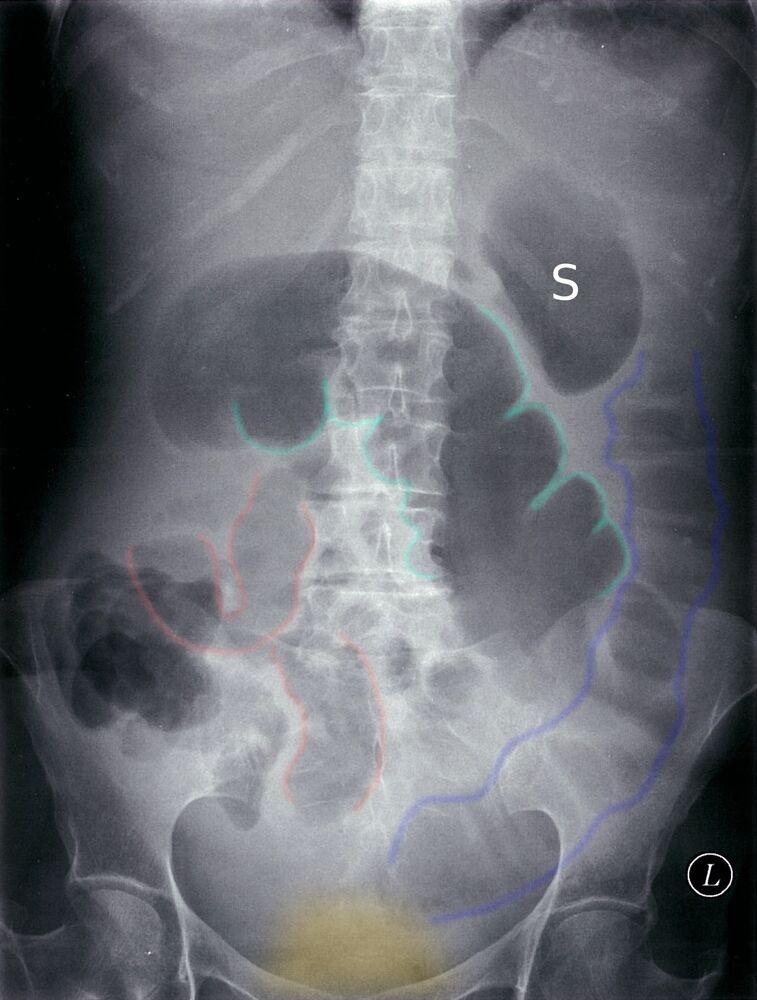

- Abdominal X-ray (best initial test) that would show dilated loops of small bowel

- Abdominal X-ray (best initial test) that would show dilated bowel (screen for free air under the diaphragm)